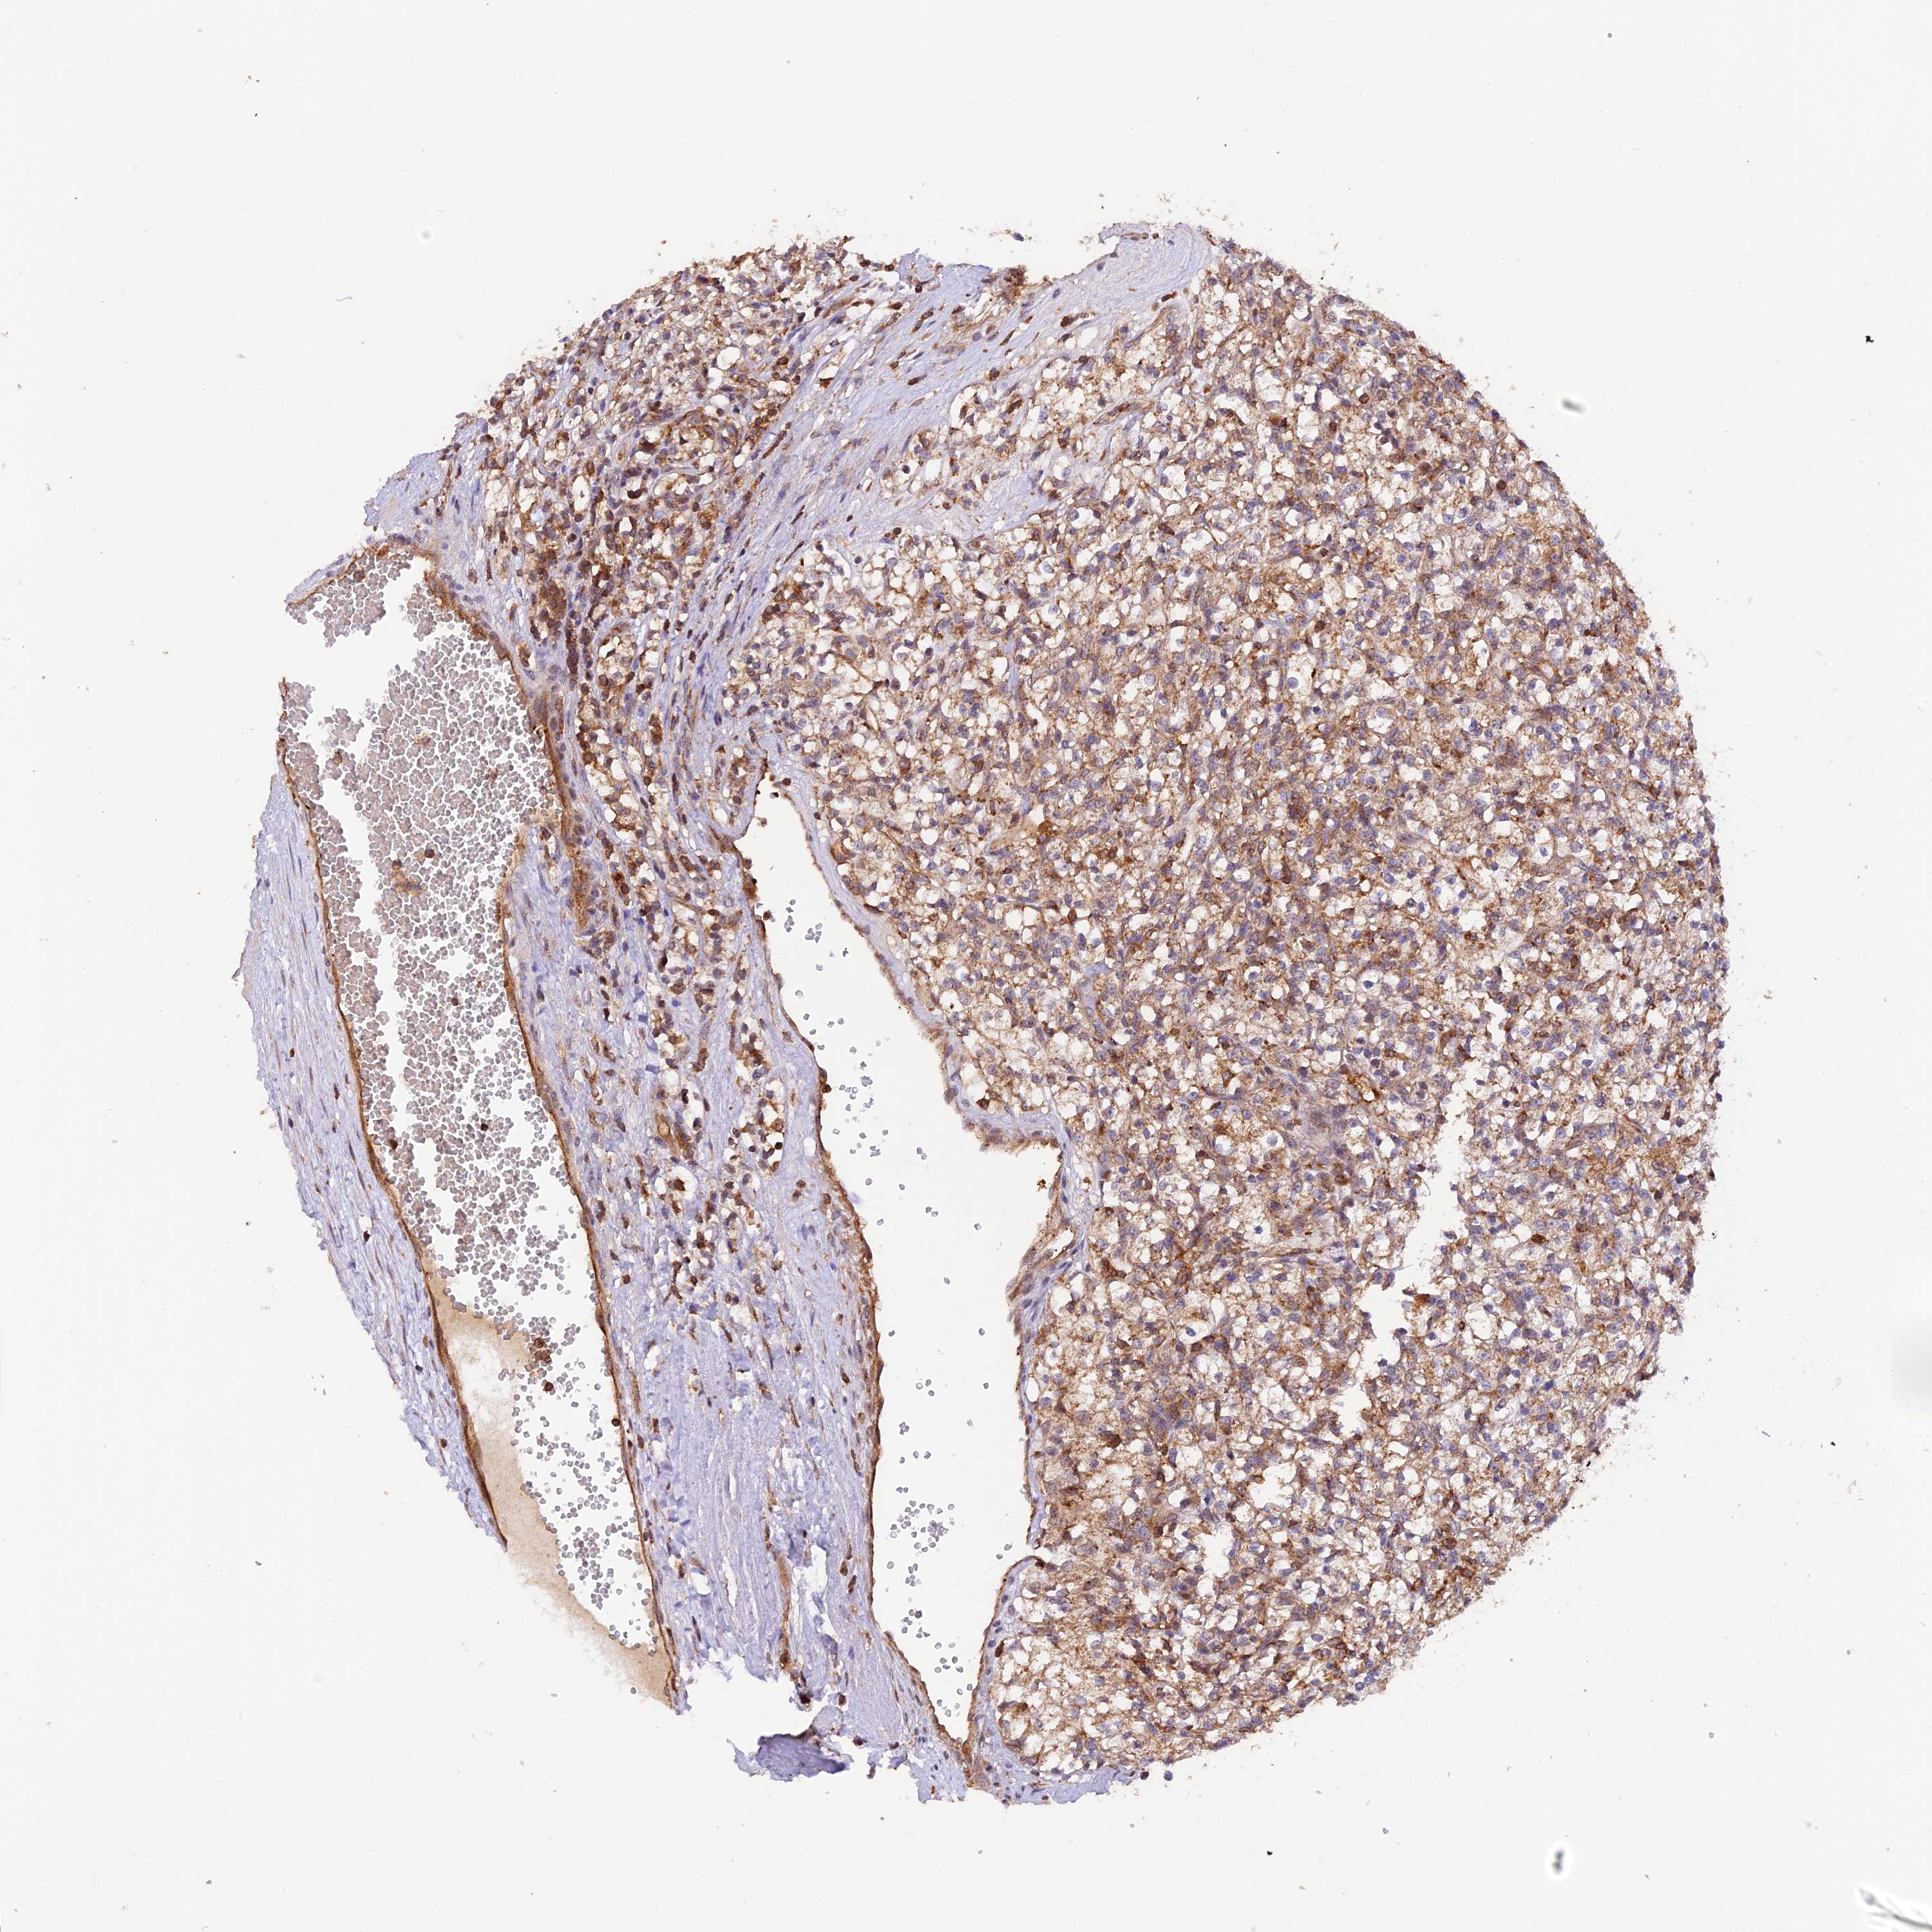

KIDNEY RENAL CLEAR CELL CARCINOMA (VALIDATION) - Interactive survival scatter ploti

The Survival Scatter plot shows the clinical status (i.e. dead or alive) for all individuals in the patient cohort, based on the same data that underlies the corresponding Kaplan-Meier plots. Patients that are alive at last time for follow-up are shown in blue and patients who have died during the study are shown in red.

The x-axis shows the expression levels (FPKM) of the investigated gene in the tumor tissue at the time of diagnosis. The y-axis shows the follow-up time after diagnosis (years). Both axes are complimented with kernel density curves demonstrating the data density over the axes. The top density plot shows the expression levels (FPKM) distribution among dead (red) and alive patients (blue). The right density plot shows the data density of the survived years of dead patients with high and low expression levels respectively, stratified using the cutoff indicated by the vertical dashed line through the Survival Scatter plot. This cutoff is automatically defined based on the FPKM cutoff that minimizes the p-score. The cutoff can be changed by dragging the vertical line or by entering a cutoff value in the square labeled "Current cut-off".

Under the Survival Scatter plot the p-score landscape (black curve; left axis) is shown together with dead median separation (red curve; right axis). Dead median separation is the difference in median mRNA expression between patients who have died with high and low expression, respectively. It is calculated as follows: median FPKM expression of dead patients with high expression - median FPKM expression of dead patients with low expression. This is intended to aid the user in visually exploring custom cutoffs and the associated p-scores and dead median separation.

Individual patient data is displayed and can be filtered by clicking on one or more of the category buttons on the top of the page. Categories describing expression level and patient information include: high, low, alive, dead, female, male and tumor stages. The scale of the x-axis can be toggled between linear and log-scale by clicking on the "x log" button. Mouse-over function shows TCGA ID, patient information and mRNA expression (FPKM) for each patient.

& Survival analysisi

Kaplan-Meier plots summarize results from analysis of correlation between mRNA expression level and patient survival. Patients were divided based on level of expression into one of the two groups "low" (under cut off) or "high" (over cut off). X-axis shows time for survival (years) and y-axis shows the probability of survival, where 1.0 corresponds to 100 percent.

PEX3 is not prognostic in Kidney Renal Clear Cell Carcinoma (validation)

Best expression cut offi

Based on the FPKM value of each gene, patients were classified into two groups and association between prognosis (survival) and gene expression (FPKM) was examined. The best expression cut-off refers the FPKM value that yields maximal difference with regard to survival between the two groups at the lowest log-rank P-value. Best expression cut-off was selected based on survival analysis .

When clicking on this number, the vertical dashed line indicating cut-off, the interactive survival plot, and the Kaplan-Meier curve will be adjusted to show results based on the best expression cut-off.

: 10.54

P scorei

Log-rank P value for Kaplan-Meier plot showing results from analysis of correlation between mRNA expression level and patient survival.

N/A

TCGA RNA samplesi

RNA-seq data is reported as average FPKM (number Fragments Per Kilobase of exon per Million reads), generated by the The Cancer Genome Atlas (TCGA) .

Normal distribution across the dataset is visualized with box plots, shown as median and 25th and 75th percentiles. Points are displayed as outliers if they are above or below 1.5 times the interquartile range. FPKM values of the individual samples are presented next to the box plot.

Average pTPM 13.5

Number of samples 100